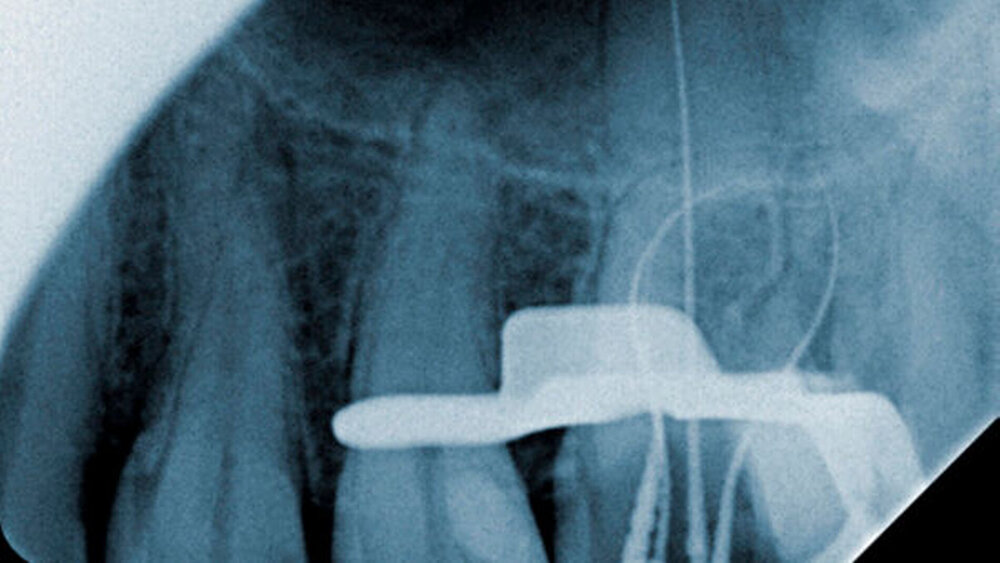

Der behandelnde Student applizierte nach Entfernung der koronalen Pulpa zunächst eine medikamentöse Einlage in die Pulpakammer und verschloss den Zahn provisorisch. Bei einem zweiten Termin wurde der Zahn unter Anästhesie und Kofferdam erneut eröffnet und die Zugangskavität ordnungsgemäß angelegt. Die angefertigte röntgenologische Messaufnahme (Abbildung 1) zeigt eindrucksvoll die Krümmung besonders der mesiobukkalen Wurzel.